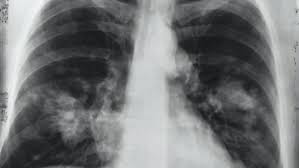

در نتیجه این بررسیها که توسط محققان کالج کینگز لندن با همکاری محققان دانشگاه تریسته واقع در ایتالیا انجام شد در اغلب موارد، ریه دچار آسیبهای شدید شده است و ساختار عادی ریه و بافتهای تنفسی تغییر کرده و به مواد فیبروتیک تبدیل شده است. تقریبا ۹۰ درصد این بیماران دارای دو ویژگی منحصر به کووید ۱۹، شامل وجود لختههای خون در رگهای ریه و سلولهای غیرطبیعی چندهستهای و بسیار بزرگ حاصل از امتزاج چندین سلول عادی بودند. این نوع شکلگیری سلولهای غیرعادی حاصل عملکرد پروتئین تاجدار ویروس است. این پروتئین موجب تحریک سطح سلولهای آلوده به ویروس و امتزاج آنها با سایر سلولهای سالم ریه میشود.

محققان با مطالعه بیشتر دریافتند ژنوم ویروس در این سلولهای غیرطبیعی و سلولهای تشکیلدهنده دیواره رگها برای مدت طولانی باقی میمانند و بقای این سلولهای آلوده به ویروس موجب تغییرات ساختاری مشاهده شده در ریهها است.